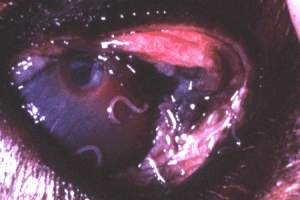

Photos Laboratoires Mérial

Elle est due au dépôt de larves d'Habronema par les mouches sur les yeux et les paupières. Les larves migrent dans la conjonctive et déterminent une conjonctivite granuleuse, analogue à la dermite précédemment décrite. Il peut se former des nodules ulcérés contenant un magma caseo-calcaire. Cette lésion peut s'aggraver en provoquant une abrasion de la cornée et une kératite inflammatoire.

Le traitement des stades larvaires au niveau des plaies fait appel à des applications locales de fenthion, de trichlorfon, voire d'anthelminthiques. Pour certaines lésions, en particulier oculaires, l'exérèse chirurgicale ou la cryochirurgie des granulomes est souvent nécessaire.